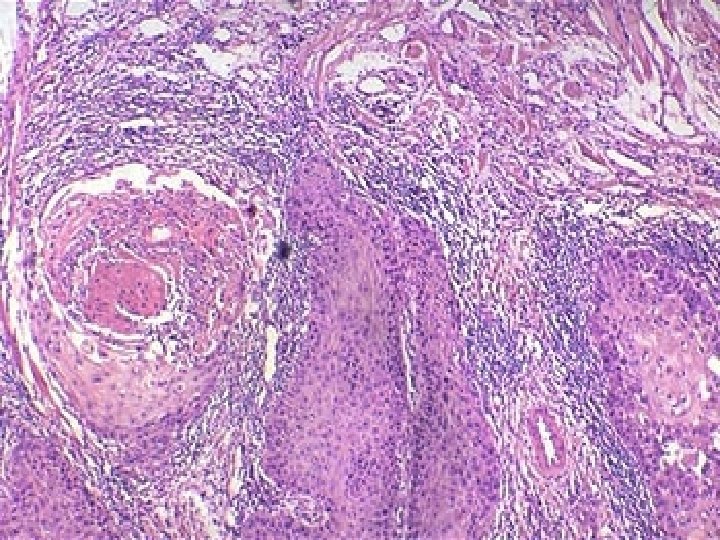

► Carencia de diferenciación…anaplasia. Tumor benigno/maligno bien diferenciado Tumor maligno Neoplasias malignas compuestas de células indiferenciadas. . anaplásicas

Anaplasia: Carencia de diferenciación. Se considera el sello de la transformación maligna. ► Literalmente: formar hacia atrás. ► No representa diferenciación inversa ► Los cánceres brotan de células madre presentes en todos los tejidos especializados. ► El cancer bien diferenciado se forma por maduración o especialización de células indiferenciadas a medida que proliferan. ► El tumor maligno indiferenciado se forma por proliferación sin maduración de las células transformadas. ►

Cambios morfológicos ► Pleomorfismo : variabilidad de tamaño y forma en células y núcleos.

► Morfología nuclear anormal: -Hipercromatismo ( núcleos oscuros por abundancia de ADN). -Relación núcleo –citoplasma alterada (normal 1: 4 -1: 6) -Formas nucleares variables. - Cromatina en grumos. - Nucleolos grandes.

Forma nuclear variada hipercromatismo nucleolos

► Mitosis: - Gran cantidad de mitosis atípicas: tripolares, cuadripolares o multipolares.

► Pérdida de la polaridad. ► Otros cambios: - Células tumorales gigantes.